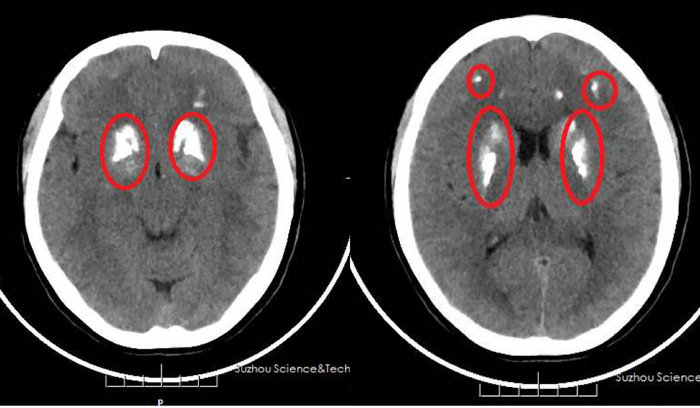

面包馒头放久了会变硬,脑子“变硬”倒是鲜有耳闻。近日,苏州科技城医院神经内科就收了一个脑子“变硬”的病人。现年30出头的周女士最近因工作劳累常常出现头晕头胀的情况,情绪烦躁容易生气,夜间睡眠也不好,症状基本上每天都会出现,有一天周女士实在忍受不了了,于是到医院检查。神经内科主治医师李瑞霞建议周女士做CT检查,这一查才发现周女士的两侧大脑及小脑出现多发对称性钙化影。

周女士的两侧大脑及小脑出现多发对称性钙化影